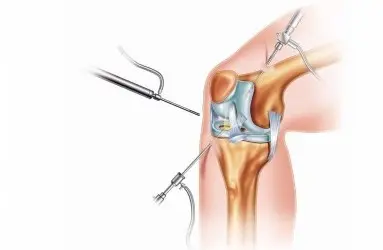

- Artroskopi